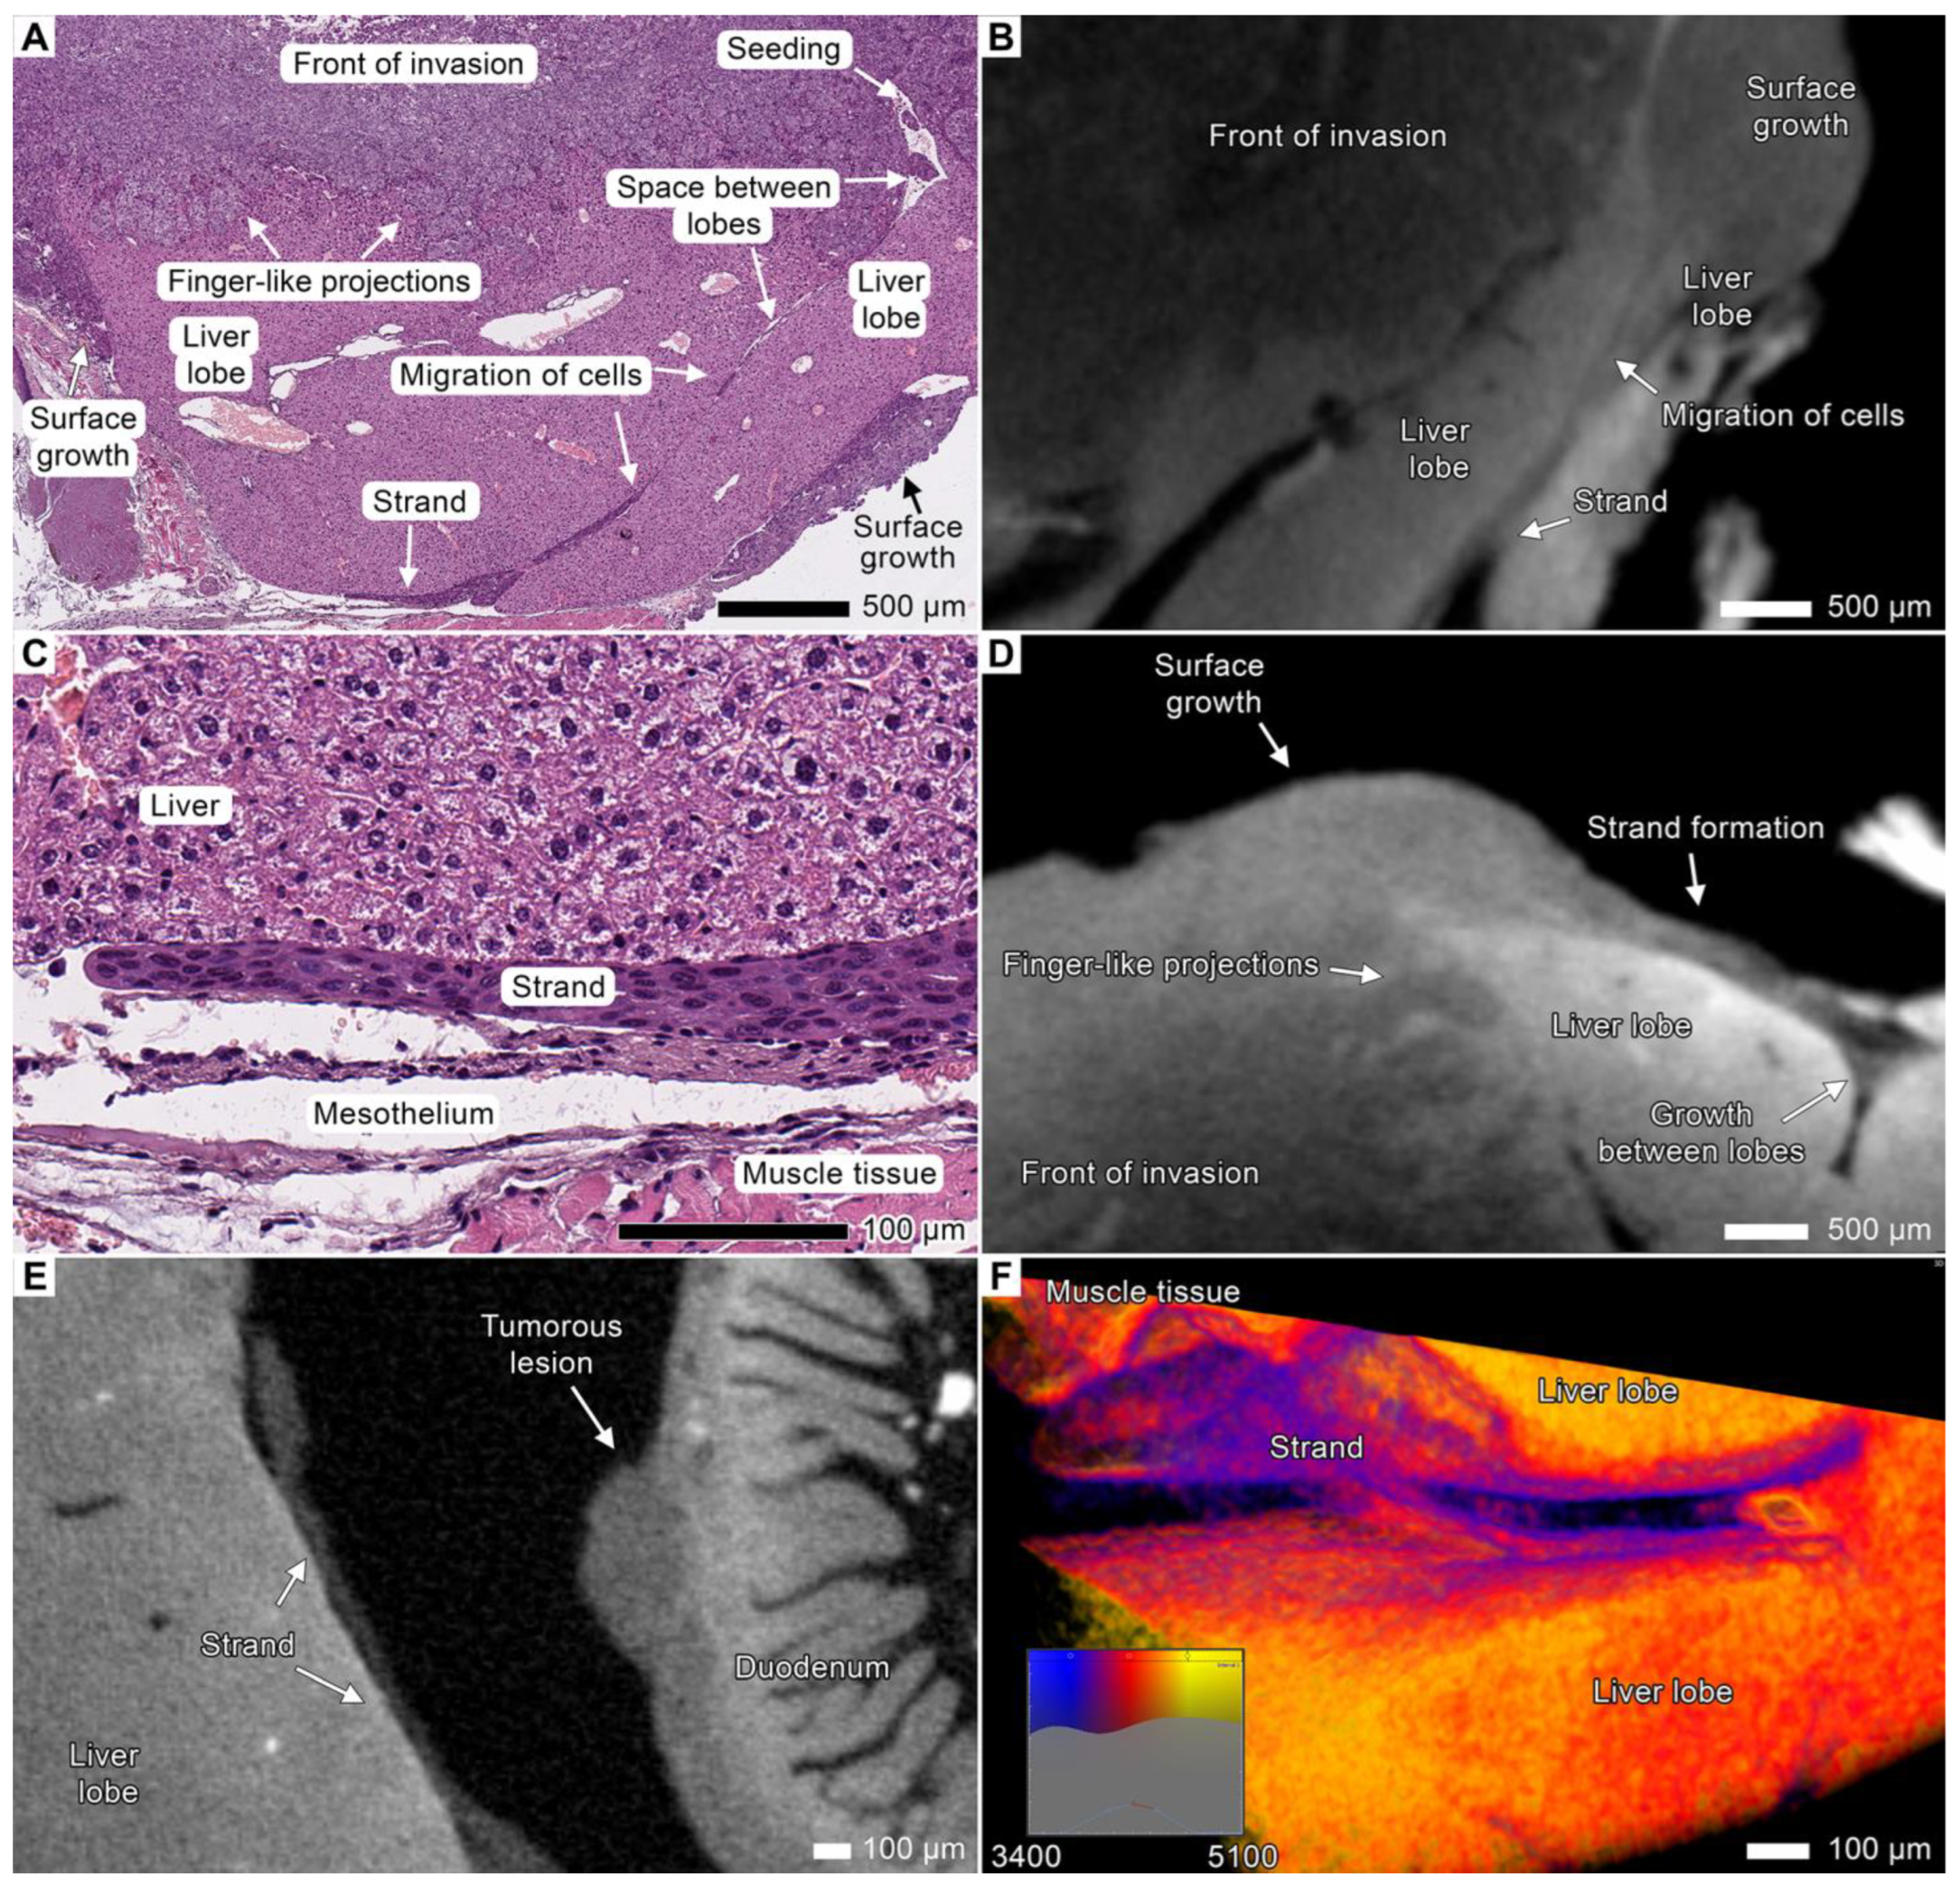

3.5. Tumor Invasion into the Liver

3.6. Peritoneal Dissemination

3.7. Stromal Connective Tissues Define Patterns of Invasion

3.8. Expanding the Concept of Tumor Clusters